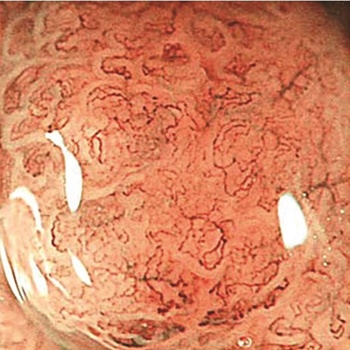

A konfokális lézer endomikroszkópia segítségével az endoszkópos képalkotás nagyítását 1000-szeres értékig tudjuk fokozni, így in vivo körülmények között a valós időben tudjuk a nyálkahártya sejtjeit, sejtalkotóit vizsgálni, s ezáltal „virtuá­lis biopsziát” végezni. A módszer során az endoszkóp munkacsatornáján vezetik le a konfokális mikroszkóp minipróbot. A megvilágításhoz 488 nm-es lézerfényt használnak, és egy 550 × 550 µm nagyságú terület 250 µm mélységben, 1 µm-nél kisebb felbontással vizsgálható át. A vizsgálathoz fluoreszcein kontrasztanyag intravénás adása szükséges.